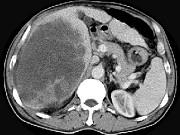

问题 男,62岁,右上腹痛半年,腹部包块,黄疸较重,AFP阴性,CT检查如图,最可能的诊断为()

选项 A.原发性肝癌 B.胆管上皮癌 C.肝囊肿 D.肝脓肿 E.肝错构瘤

答案 B